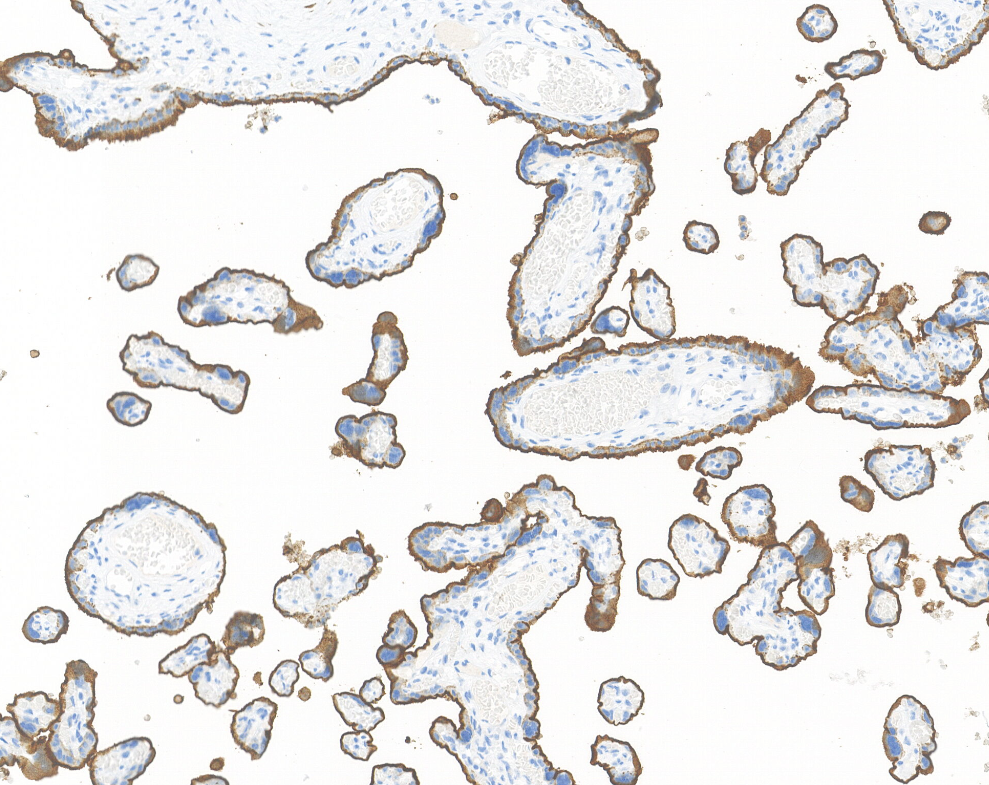

Contrôle positif : Tissu placentaire